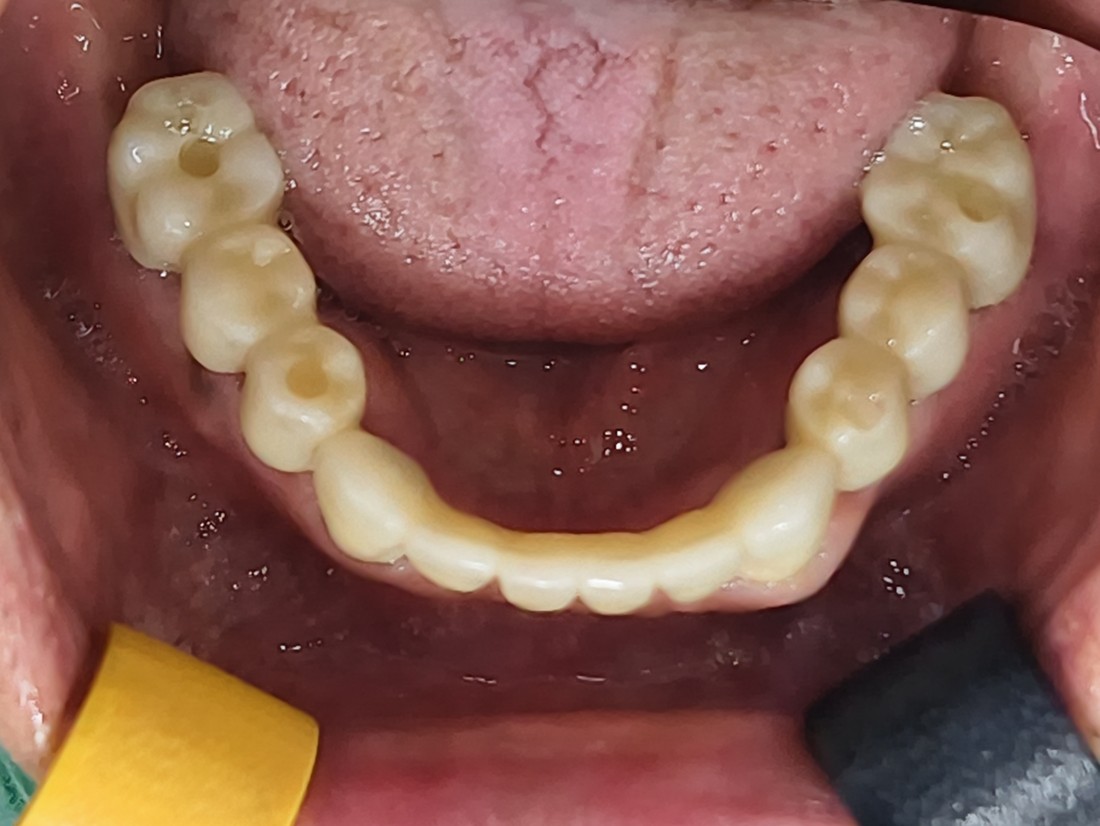

단 두 번의 수술만으로

광주 전체임플란트

완성할 수 있는 비결은

광주 전체임플란트 치과에서는

전체임플란트를 완성하고 있습니다.

자동차가 네비게이션을 따라

정확한 목적지에 도착하듯,

디지털가이드 임플란트를 활용하여

미리 임플란트를 3D 가이드로 제작하기 때문에

정확한 깊이, 정확한 위치에

임플란트 식립이 가능합니다.

광주 전체임플란트를 디지털가이드 임플란트로

완성하고 있기 때문에

잇몸절개를 하지 않거나 (무절개) 혹은

최소한으로만 절개하고 있어서

임플란트 수술 시간이 짧으며,

붓기 / 출혈 / 통증이 매우 줄어듭니다.